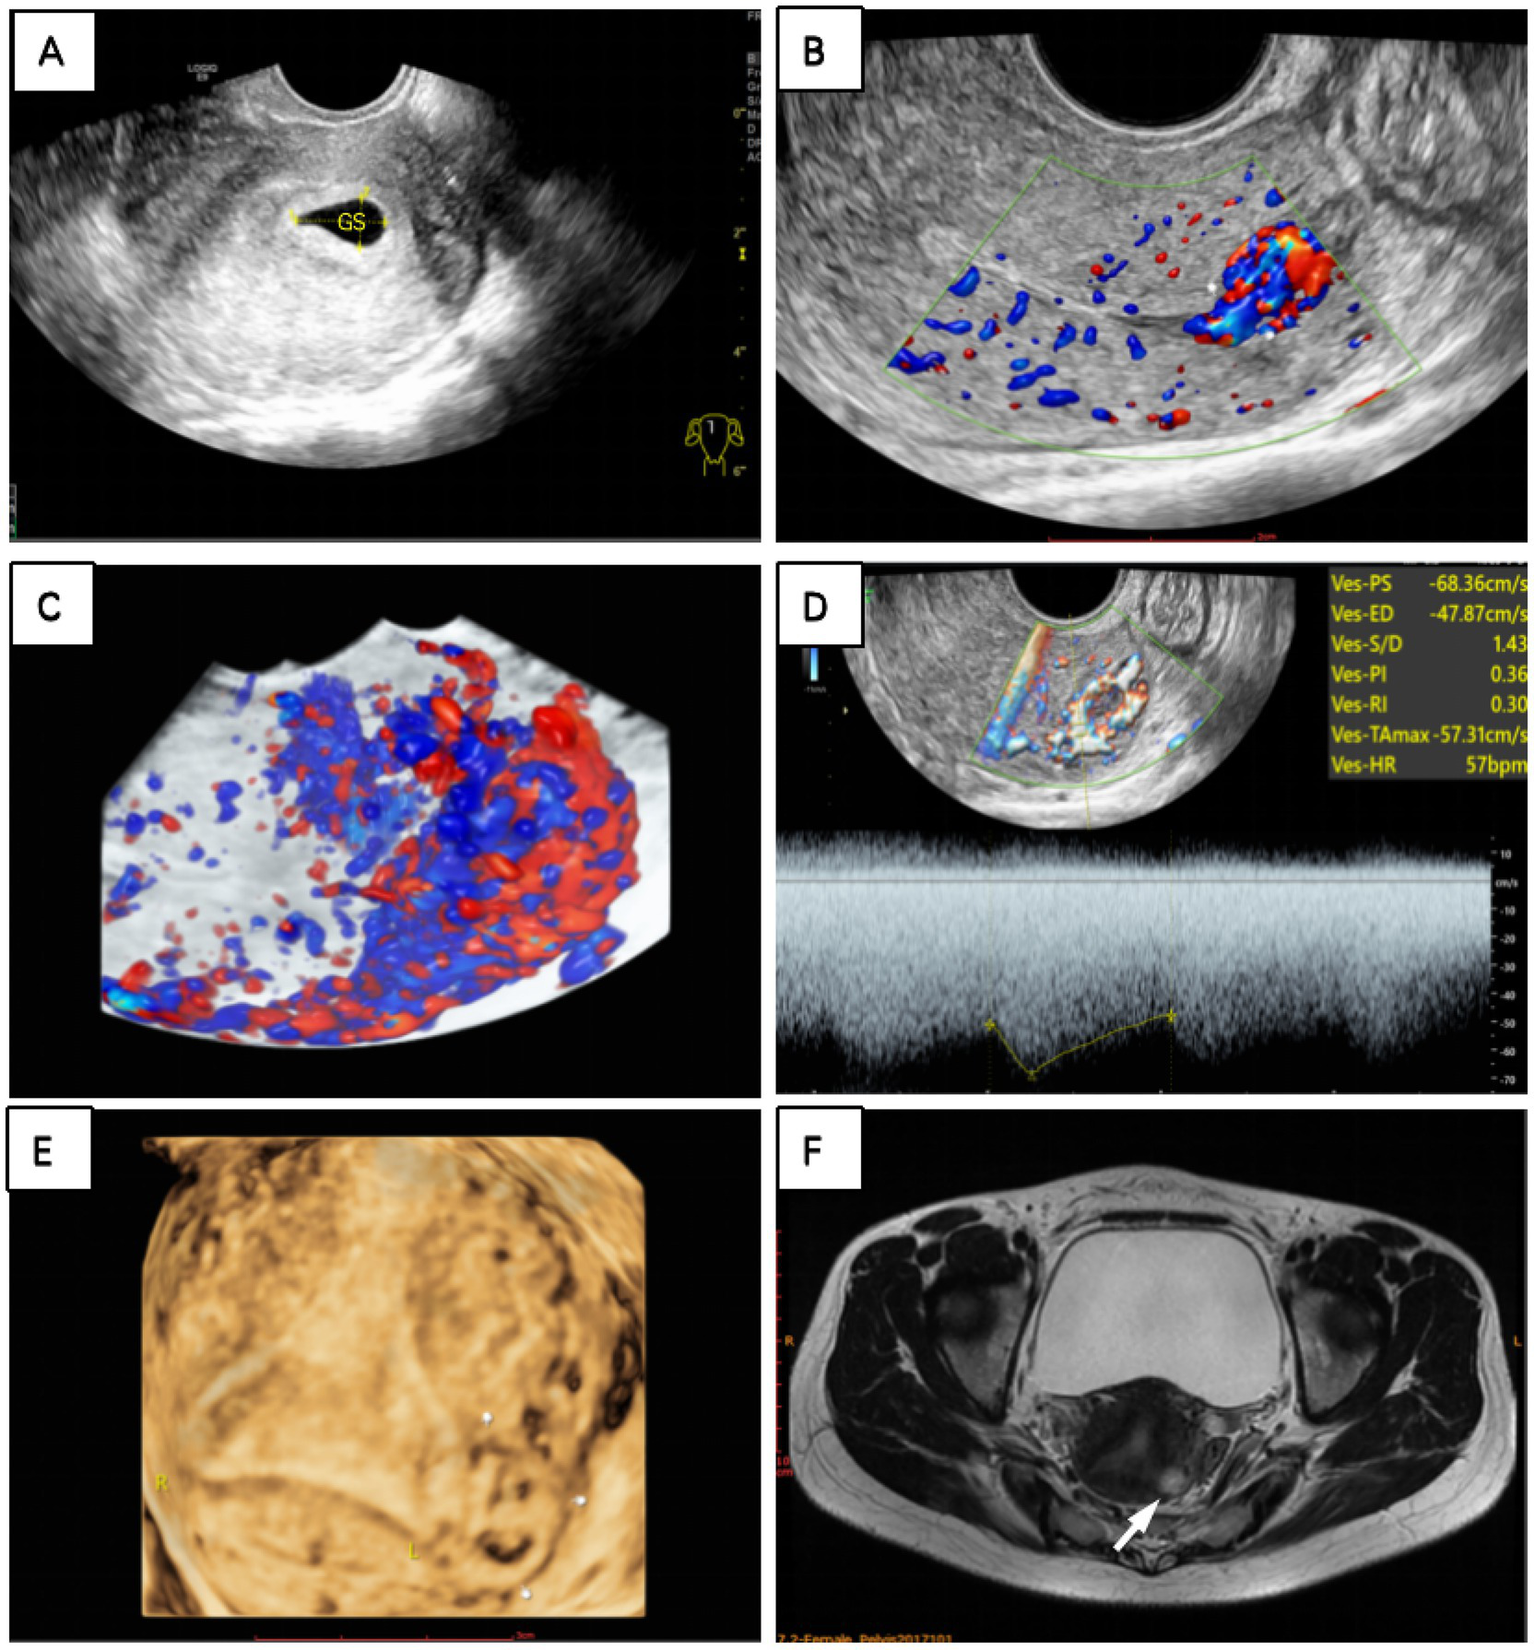

However, a 2-month follow-up revealed a paradoxical elevation in serum β-hCG levels to 3,069 mIU/mL, prompting further diagnostic evaluation. Initially, we suspected that an incomplete medical abortion with retained tissue was the cause, so we performed a two-dimensional TVS. However, it did not reveal any obvious gestational sac or mass in the uterine cavity, but abundant blood flow signals extending from the uterine cavity to the muscularis propria were detected on the CDFI mode. Three-dimensional TVS revealed an abnormal echogenic mass at the fundus of the uterus, which appeared on color Doppler flow imaging as a garland of abundant and disorganized flow signals extending into the muscularis propria. The mass showed a low-resistance, high-velocity blood flow spectrum, with a resistance index of 0.30, a pulsatility index of 0.36, and a peak systolic velocity of 68.36 cm/s (Figure 3).

Figure 3

(A) A hypoechoic area was observed in the uterus on transvaginal ultrasound. Two months after medication abortion, (B) CDFI and (C) three-dimensional flow imaging revealed abundant blood flow signals resembling vascular pools at the uterine fundus. (D) Spectral Doppler revealed high-speed, low-resistance arteriovenous fistula-like flow. (E) Three-dimensional ultrasonography and (F) MRI T2-weighted sequence revealed a gestational sac within the left myometrium, outside the endometrial cavity (white finger and arrow pointing to the gestational sac).